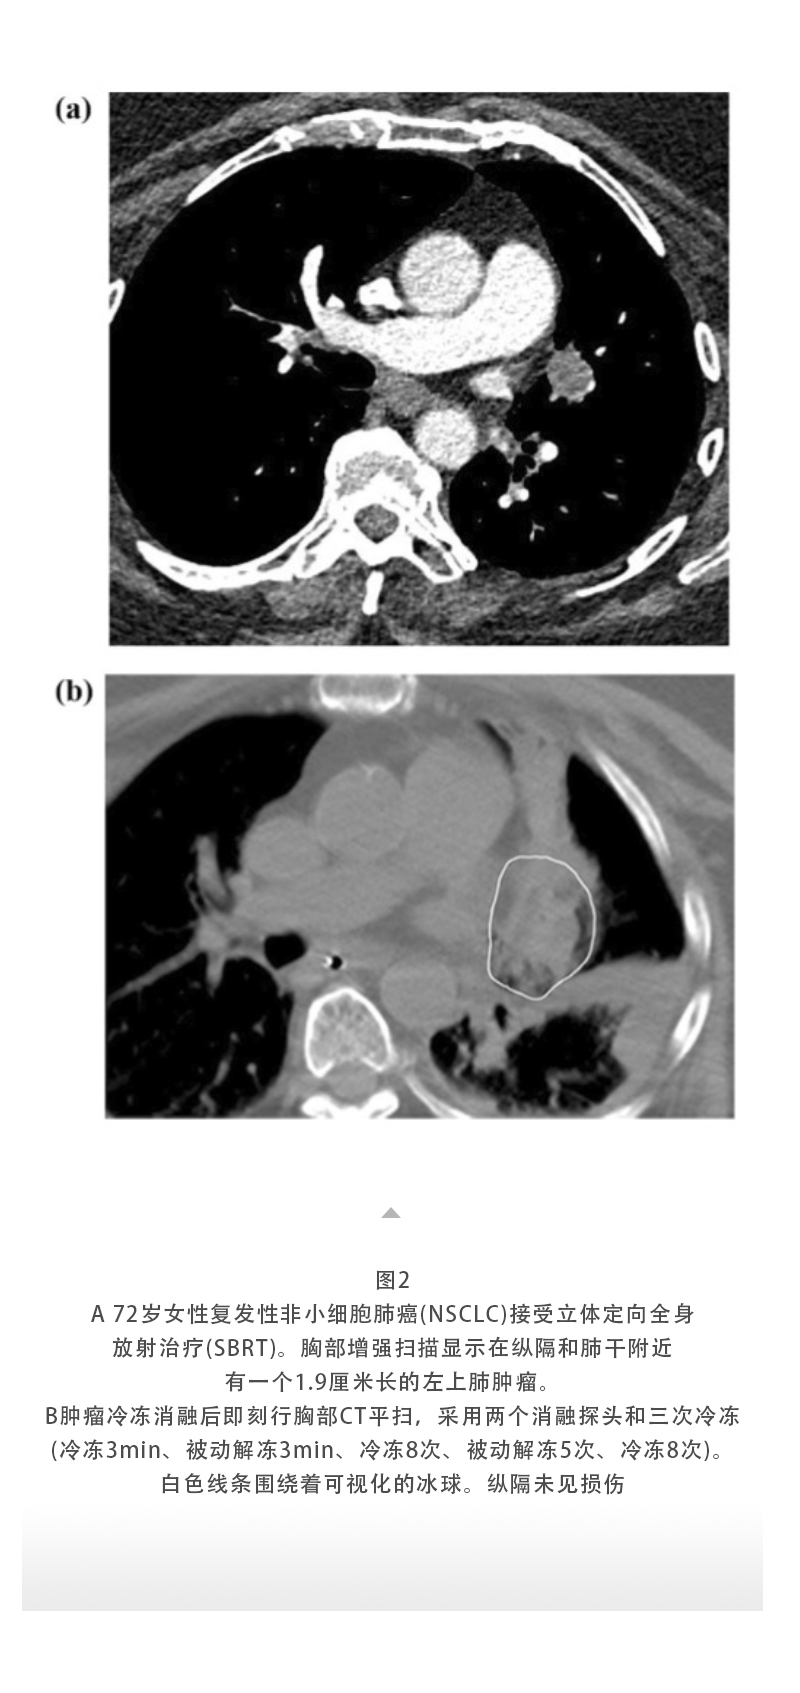

【HYGEA·科研資訊】冷凍消融治療肺癌

發布時間:2025-10-15 | 作者:海杰亞 | 瀏覽次數:163